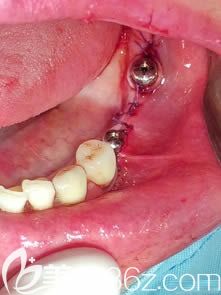

那么什么是种植牙二期修复手术呢?——请听杨秀洪医生的讲解:

杨秀洪:通常我们将种植体埋入在颌骨内称为种植一期手术。然后根据一期手术后骨的愈合情况,然后拍X光片,判断骨密度的情况后,在一期手术3-6个月之后,进行二期手术的修复。二期手术修复也是采用局麻的方式,将一期植入的种植体,覆盖螺丝后,在这个上面旋入愈合基台,一般愈合基台旋入大概两个星期后,再进行上部结构的修复。